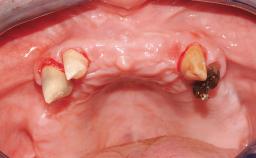

Conventional Loading of Eight Implants in the Maxilla and Final Restoration with a Full-Arch Gold-Ceramic FDP

A 35-year-old Caucasian female presenting with advanced periodontal disease involving both the maxillary and the mandibular dentition was referred for evaluation. The patient, a non-smoker in good general health, requested treatment for recurrent periodontal abscesses, tooth mobility, and discomfort during chewing, as well as restoration of her missing teeth with a fixed prosthesis to improve mastication and esthetics. All residual maxillary teeth exhibited plaque deposits, deep pockets, bleeding on probing, and class III mobility and were evaluated as hopeless. All residual mandibular teeth except tooth 37 could be maintained after periodontal therapy.

Bone Volume Horizontally and vertically sufficient Horizontally deficient Deficient vertically or deficient vertically AND horizontally

Bone Volume Deficient vertically or deficient vertically AND horizontally